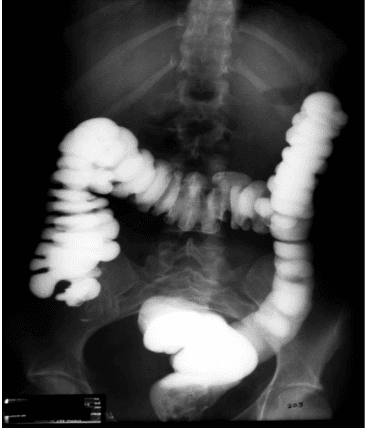

- Rút dây dẫn và bơm thuốc đối quang tan trong nước để dễ dàng quan sát mức độ và vị trí hẹp.

- Bơm thuốc đối quang qua ống thông để xác định vị trí, mức độ, chiều dài đoạn hẹp.